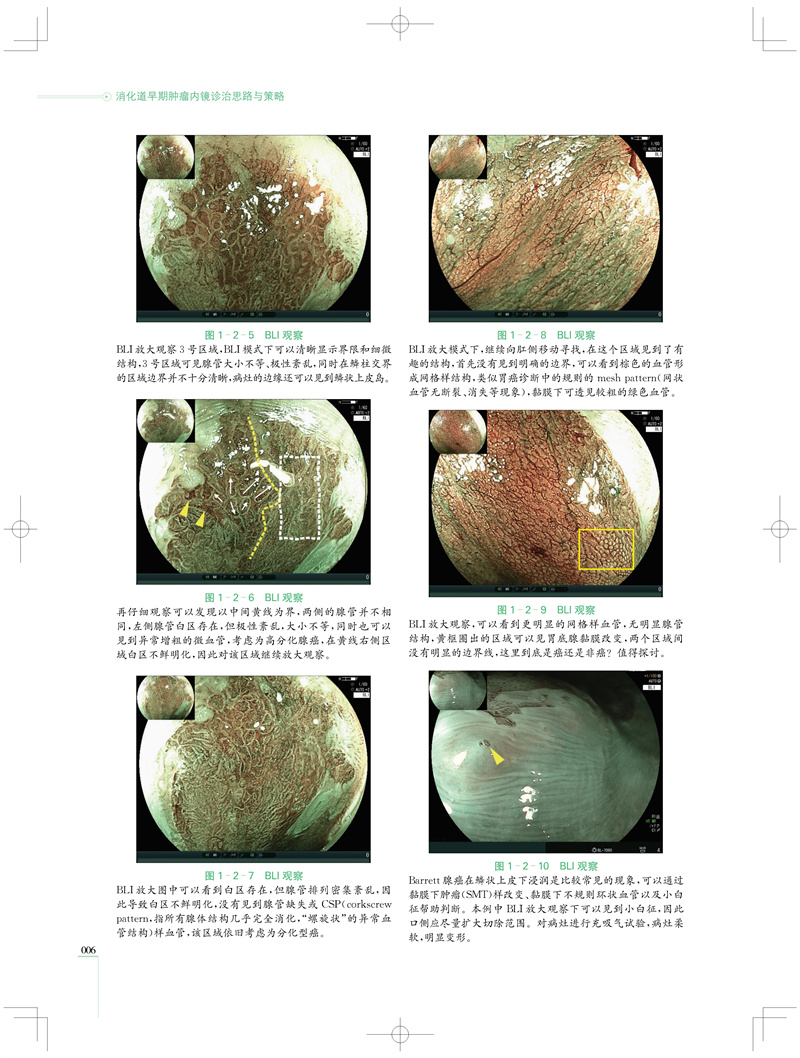

本书精心收录“秀出镜彩”LCI/BLI菁英病例大赛中的86例消化道早期肿瘤病例的诊治资料,展示了各类病变于LCI/BLI下呈现的典型图像特征,且均附有病理论证及术者诊疗心得等。借此,读者可直观且深入地研习并精准掌握各类消化道早期肿瘤病变的内镜诊断标准与分型方式,明晰其临床诊治思路。 本书图文并茂,资料丰富,其中68个病例配有完整的讲解视频,对病例详尽的诊治流程予以深入阐释。在阅读纸质文本之际,读者可通过扫码观看视频,亲临其境般深刻体悟在诊治每个病例的过程中所遇到的难点与困惑,从而为其临床工作带来有益启示,有效提升对消化道肿瘤病变的诊疗水平。